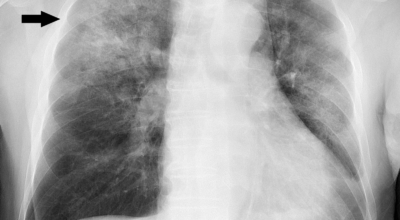

폐렴은 폐의 감염으로 인해 발생해요. 대부분의 감염은 박테리아나 바이러스에 의해 발생하지만 종종 원인을 찾을 수 없어요. 감기나 독감에 의해 유발될 수 있고, 이로 인해 세균이 폐에 접근할 수 있어요. 세균성 폐렴은 폐렴구균 박테리아에 의해 발생할 수 있어요. 이것은 가장 심각하고 잠재적으로 생명을 위협하는 유형의 폐렴 중 한가지이예요.

폐렴을 유발하는 다른 유형의 박테리아는 헤모필루스 인플루엔자와 모락셀라 카타랄리스 이지요. 바이러스성 폐렴은 여러가지 바이러스에 의해 발생해요. 가장 흔한 것은 인플루엔자 바이러스, 인간 아데노바이러스 또는 호흡기 세포융합 바이러스이지요.